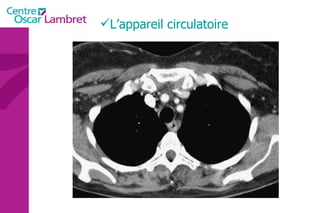

L’appareil circulatoire L’appareil circulatoire  s’appuie sur un véritable réseau aussi étendu que précis. Sous l’impulsion du  coeur , chef d’orchestre vital, les artères et les veines assurent le transport du sang indispensable à tout notre organisme.  Les artères  apportent le sang riche en oxygène et en nutriments à l’ensemble des tissus de l’organisme.  Les veines  doivent rapporter le sang appauvri en oxygène vers le coeur puis les poumons. Des  poumons , il repasse dans le coeur qui le propulse de nouveau via les artères à tout l’organisme.

Le cœur  se situe au milieu du thorax, sur le diaphragme, la pointe tournée vers la gauche. L’appareil circulatoire